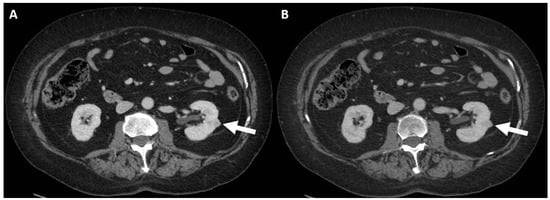

4. Computed Tomography Assessment

4.1. Lesion Density

4.2. Macroscopic Fat

4.3. Enhancement